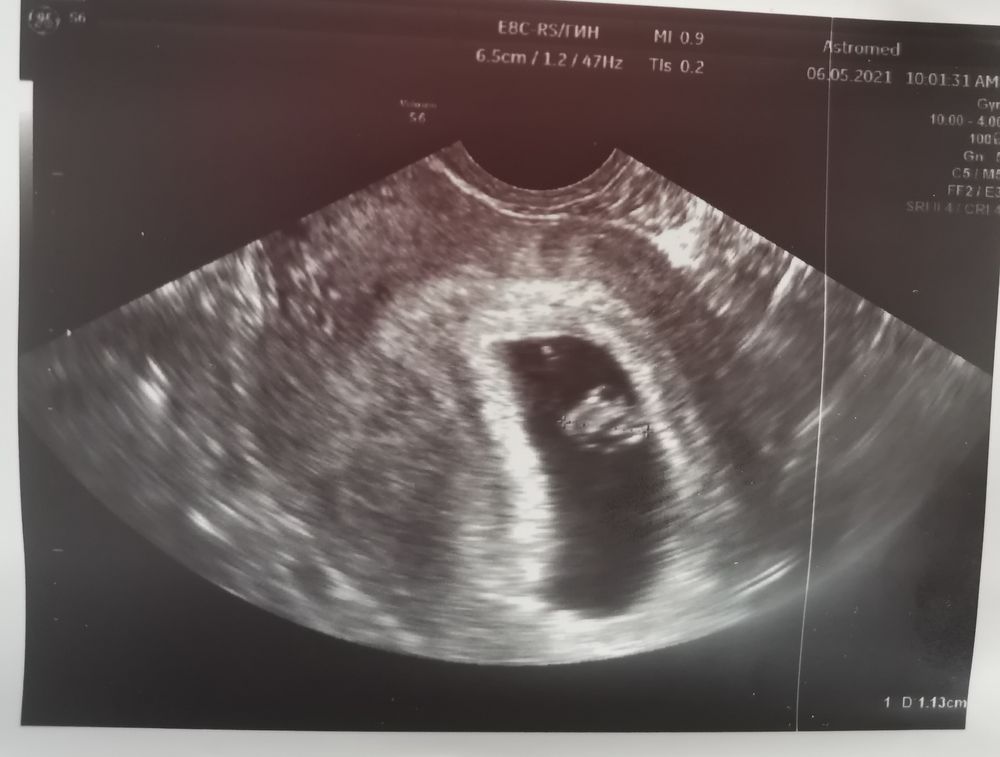

06.05.2021

У меня сошлось. У вас думаю девочка

Этот метод не работает, говорят девочки,те кто пробовал здесь. Девочка по этому методу. Но насколько этот метод работает хз…